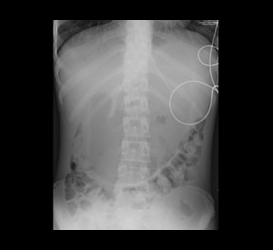

We selected this case because of its unique presentation and associated findings. The patient’s medical managing team was surprised when we communicated to them the finding of suspected gastric outlet obstruction on abdominal radiograph and recommended placement of an enteric tube with order for immediate cross-sectional imaging. They told us that the working diagnosis was constipation and were planning to treat it conservatively with enema. Follow-up computed tomography (CT) confirmed the upper gastrointestinal (GI) obstruction and revealed the underlying cause to be superior mesenteric artery (SMA) syndrome. The team was then able to elicit a history of significant rapid weight loss from the mother.

Reading plain radiographs is an art that needs to be mastered by all radiologists. New trainees should be aware of the subtle, but information-laden clues to diagnosis that can show up on plain films and direct next steps of management.

We were excited when our Attending, Dr. Hammill, agreed with our diagnosis. However, we were confused with the liver and splenic ischemic foci apparent on CT as this is not a phenomenon ever described to be associated with SMA syndrome. Dr. Hammill directed our attention to the compression of the retroperitoneal vascular structures including branches of the celiac artery by the markedly distended stomach.